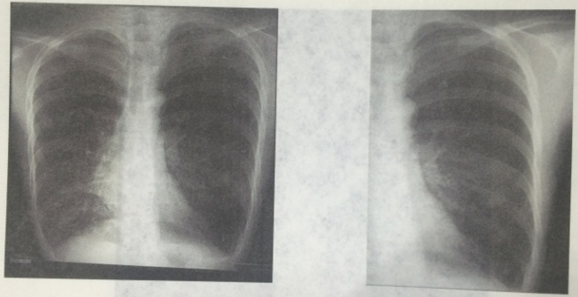

西醫(yī)臨床答辯:根據(jù)X線片做出臨床判讀(5分)